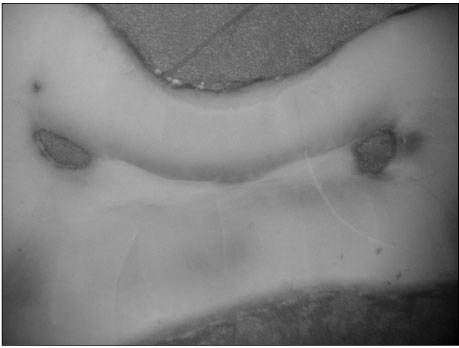

Figure 2

Photograph of the physiologic foramen of mesial root (×60)

Figure 2 Photograph of the physiologic foramen of mesial root (×60)